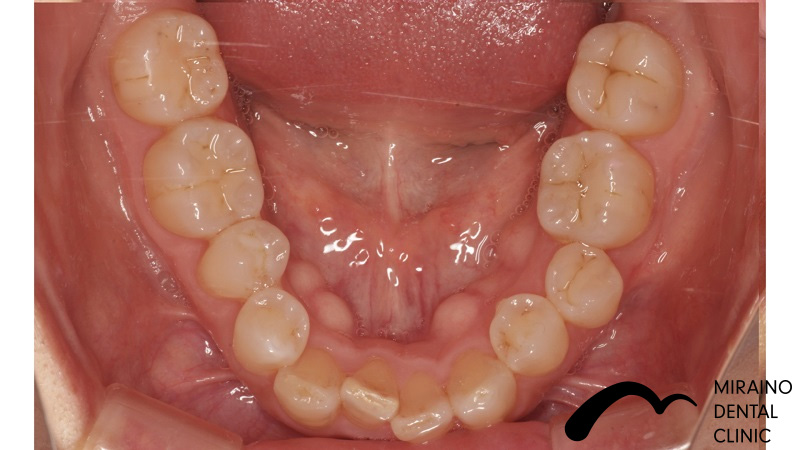

被せ物&詰め物・メタルフリークラウン&インレーの症例

| 施術名 | 被せ物・メタルフリークラウン |

| 施術の概要 | 銀歯のところから変な匂いがするということで来院されました。 5年以上前に治療してもらった歯科医院では「銀歯による虫歯治療のデメリット」を 聞いたことがなかったとのこと、でした。 銀歯が大きく歯が割れてしまうリスクが高く、次に再発した際は神経を取らないといけなくなる可能性が高いため、 なるべく再発しにくい歯科治療を希望され、汚れのつきにくい素材[ジルコニアセラミック]で被せ物を装着しました。 |

クリックして詳細を表示

| 施術の内容 | 根っこの治療後など歯の表面を削って強度の高く、汚れの付きにくいジルコニアクラウンを被せて歯を補強します。 |

| 1歯あたりの治療費 | 80,000~150,000円 |

| 施術名 | 詰め物・メタルフリーインレー |

| 施術の概要 | 銀歯のところから変な匂いがするということで来院されました。 5年以上前に治療してもらった歯科医院では「銀歯による虫歯治療のデメリット」を 聞いたことがなかったとのこと、でした。 銀歯が大きく歯が割れてしまうリスクが高く、次に再発した際は神経を取らないといけなくなる可能性が高いため、 なるべく再発しにくい歯科治療を希望され、汚れのつきにくい素材[ジルコニアセラミック]で被せ物を装着しました。 |

クリックして詳細を表示

| 施術の内容 | 銀歯は歯より硬すぎる、歯を腐食させる作用があることから約5年で再発すると言われています。 ラバーダムを用いて唾液による接着不良のリスクを排除し完全に水分を排除した状態でムシ歯治療を行います。 型取りを行い、技工士によって汚れの付きにくいセラミックで形を再現している |

| 1歯あたりの治療費 | 1歯:50,000円 |